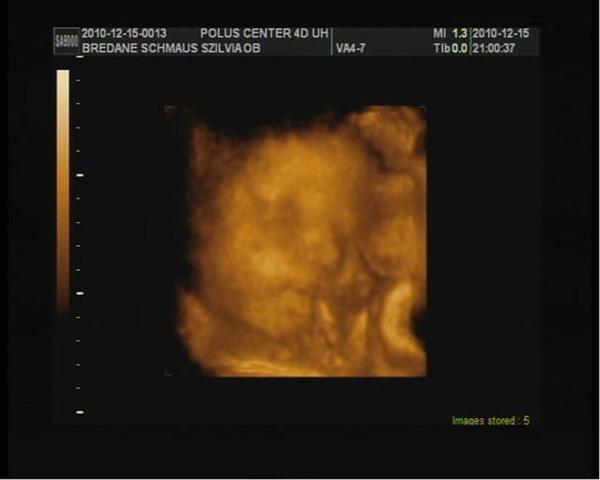

37.hét_02